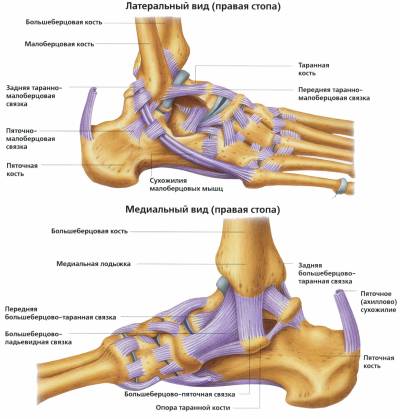

Анатомия голеностопа: Сухожилия и их строение